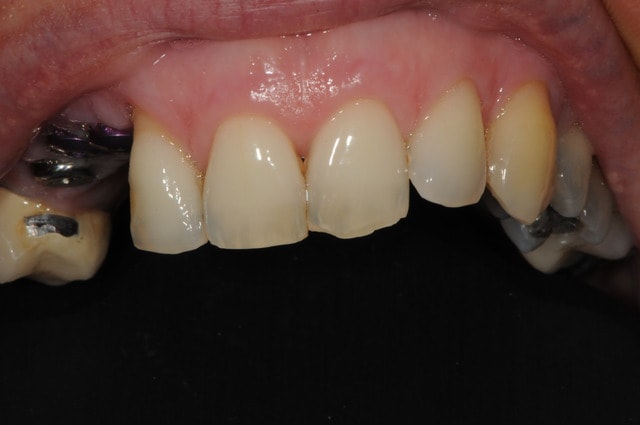

très joli dudule...j'aurai fait pareil...et pas de conjonctif palatin non plus dans ce cas en prime intention...mieux vaut se le réserver pour la phase implantaire (à la pose ou au désenfouissement si technique 2 temps

bien aussi béo...des photos du cas fini?